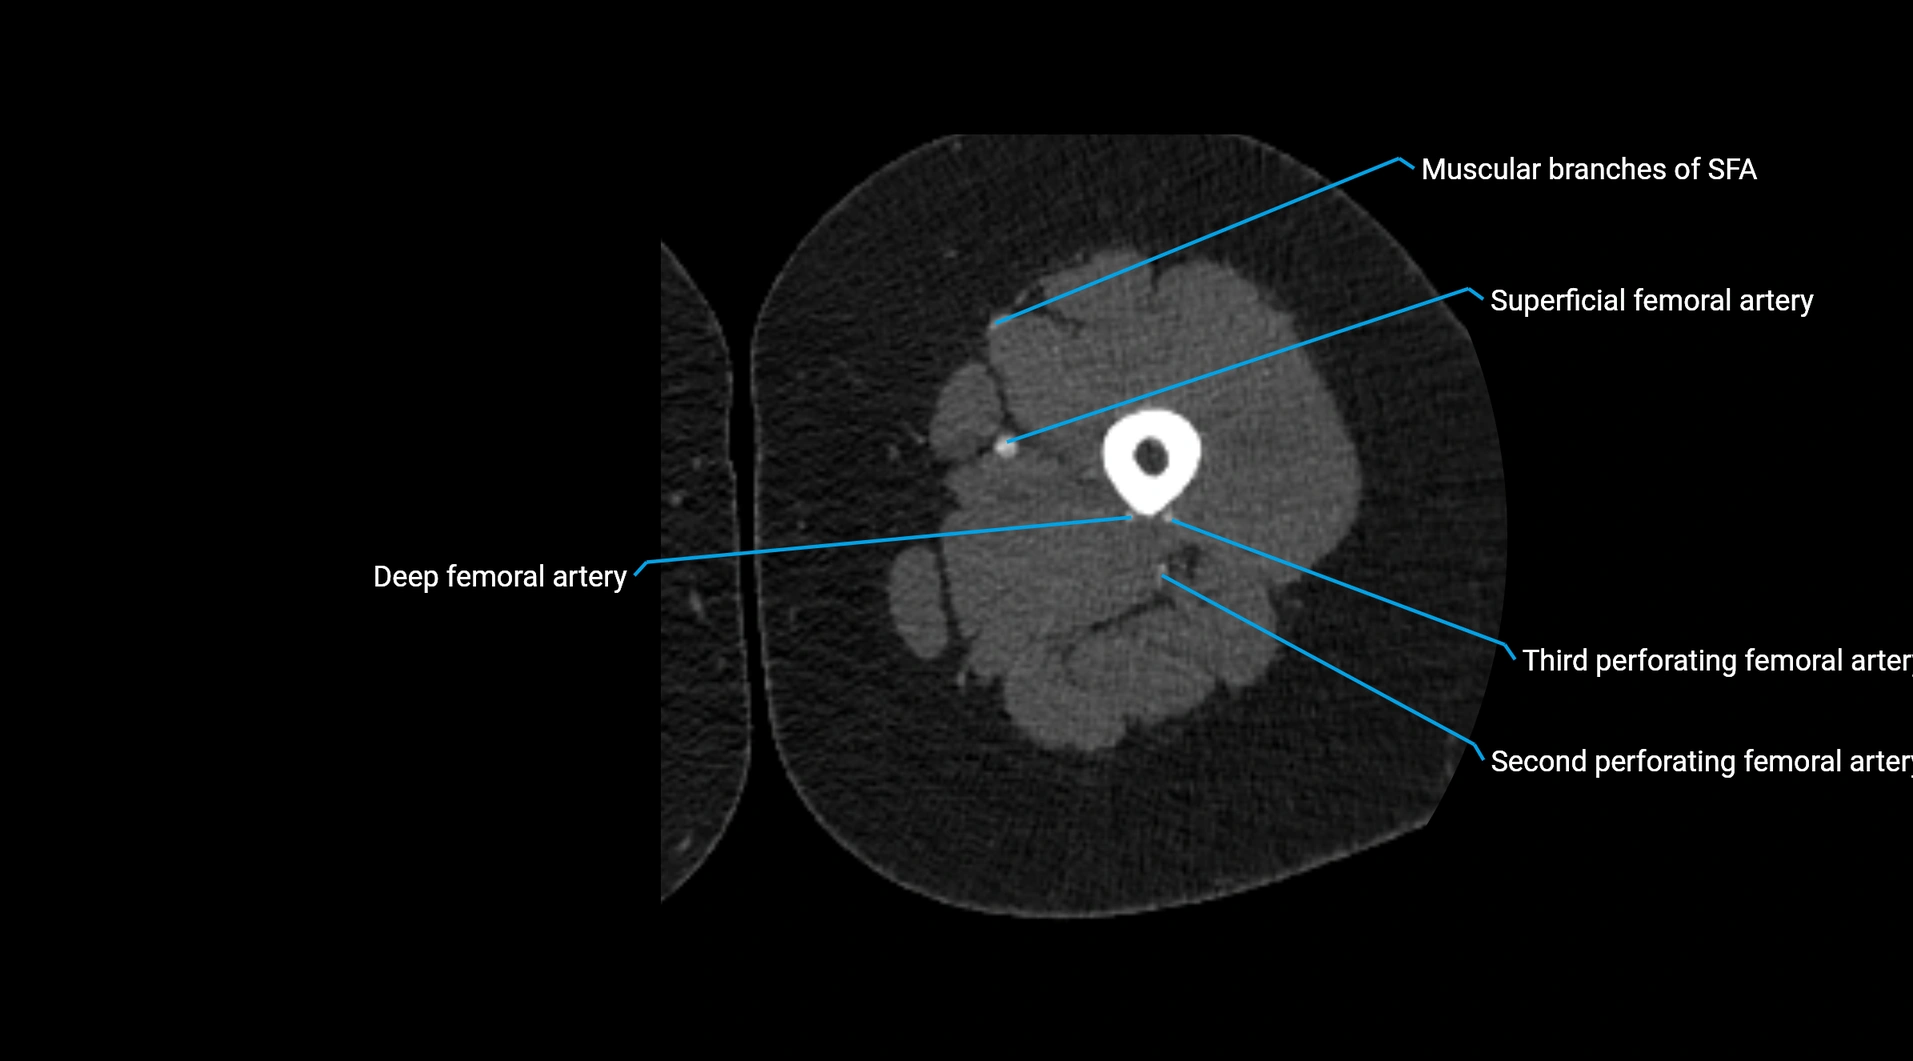

CT images

image